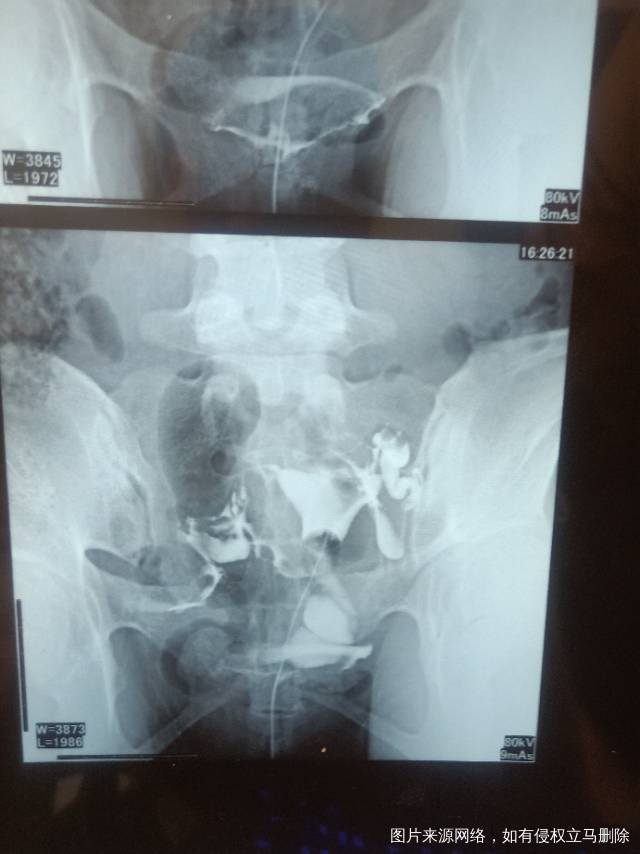

请问医生我这个造影有没有输卵管积水呀影不影响